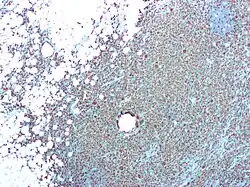

Osteoclasts are the most prominent examples of MGCs and are responsible for the resorption of bones in the body. Like other MGCs, they are formed from the fusion of monocyte/macrophage precursors.[4] However, unlike other MGCs, the fusion pathway they originate from is well elucidated. They also do not ingest foreign materials and instead absorb bone matrix and minerals.

Osteoclasts are typically associated more with healthy physiological functions than they are with pathological states. They function alongside osteoblasts to remodel and maintain the integrity of bones in the body. They also contribute to the creation of the niche necessary for hematopoiesis and negatively regulate T cells. However, while the primary functions of osteoclasts are integral to maintaining a healthy physiological state, they have also been linked to osteoporosis and the formation of bone tumors.[5]

Osteoclasts were discovered in 1873.[3] However, it was not until the development of the organ culture in the 1970s that their origin and function could be deduced. Although there was a consensus early on about the physiological function of osteoclasts, theories on their origins were heavily debated. Many believed osteoclasts and osteoblasts came from the same progenitor cell. Because of this, osteoclasts were thought to be derived from cells in connective tissue. Studies that observed that bone resorption could be restored by bone marrow and spleen transplants helped prove osteoclasts' hematopoietic origin.[3]